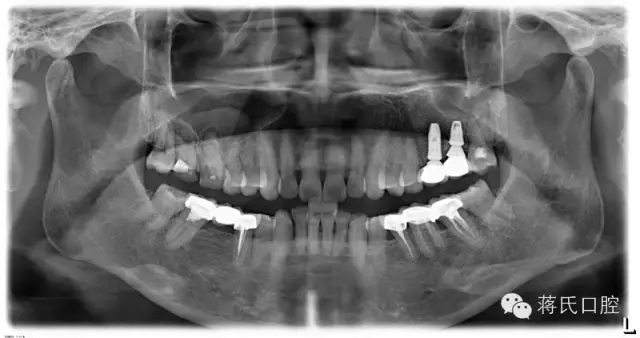

12.修復(fù)后全景片